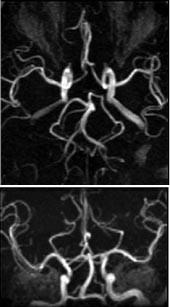

Intrakraniale kar

Kontrastforsterket MRA har foreløpig for dårlig romoppløsning for intrakranialt bruk. Den MRA-metoden som er best egnet for fremstilling av intrakraniale arterier, er 3D-innstrømnings-MRA (fig 3). Ved hjelp av denne metoden kan man påvise stenoser og okklusjoner av de større arteriene. Både MRA og CT-angiografi kan fremstille intrakraniale aneurismer med diameter på 5 mm eller mer med stor nøyaktighet (10, 11), for mindre aneurismer synes CT-angiografi å være noe bedre enn MRA. De ikke-invasive metodene kan bidra ved planlegging av behandling av aneurismer (kirurgisk eller radiologisk intervensjon), men metodene har ennå ikke kunnet erstatte kateterangiografi (12). Ved intrakraniale arteriovenøse malformasjoner er MR-snittbilder den metoden som best viser den anatomiske lokaliseringen av nidus (13). MRA kan gi en bedre anatomisk oversikt over hele malformasjonen, særlig om man benytter fasekontrast-MRA, som gir best fremstilling av både arterie- og venesiden. Både kirurgi og endovaskulær embolisering krever imidlertid en detaljfremstilling som bare kan gis av kateterangiografi.

Arteriosklerotisk sykdom i halsarteriene er en av de vanligste indikasjonene for MRA. Ultralydundersøkelse (med fargedoppler og spektraldoppler) er et godt ikke-invasivt alternativ, og for stenoser i carotisbifurkaturen synes denne metoden å være nokså likeverdig med MRA (14). Ultralydundersøkelsens svakhet i forhold til MRA er begrenset anatomisk dekning, verken den intrakraniale del av halsarteriene eller avgangen fra aortabuen kan fremstilles adekvat. Fremstillingen av vertebralisarteriene blir også ufullstendig. Inntil nylig har innstrømnings-MRA vært den foretrukne MRA-metoden for fremstilling av carotis- og vertebralisarteriene, men den er i ferd med å bli erstattet av kontrastforsterket MRA. Sistnevnte metode er mindre ømfintlig enn innstrømnings-MRA for ulike artefakter, som bl.a. kan føre til overestimering av stenosegrad, og den kontrastforsterkede varianten gir også en mye bedre fremstilling av arterieavgangene fra aorta (fig 5). MR med innstrømnings-MRA kan erstatte kateterangiografi ved mistanke om carotisdisseksjon (15), det er foreløpig liten erfaring med kontrastforsterket MRA ved denne indikasjonen. Kontrastforsterket MRA gir en god fremstilling av a. subclavia og er et godt alternativ ved spørsmål om stenose i skalenusporten. To kontrastinjeksjoner med redusert dose gjør det mulig å undersøke arterien med både løftet og senket arm i samme seanse. Halsvenene kan fremstilles med 2D-innstrømnings-MRA eller med kontrastforsterket MRA, men der det er spørsmål om trombosering eller venens relasjon til en tumor, vil ofte ultralydundersøkelse være tilstrekkelig. MRA gir imidlertid en bedre anatomisk oversikt og er også mer reproduserbar. 2D-innstrømnings-MRA er også